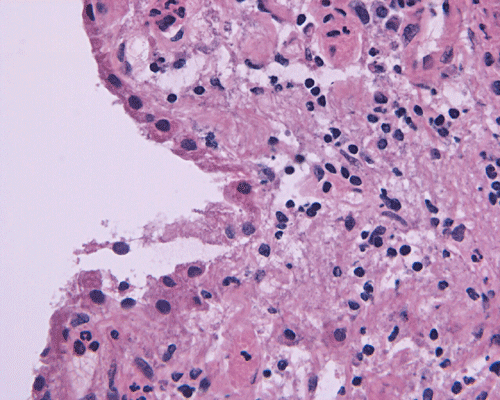

Intraoperative consultation: The specimen is that of a streotactic biopsy and is very small. The intraoperative cytologic preparation was rather hypocellular. Small clusters of cells with bland nuclei and foamy cytoplasm are present and they are highly suggestive of foamy histiocytes (Panel C). On frozen section, there are many small lymphocytes in a "pink" background that can be a granulomatous process (Panel D). In some areas, many foamy macrophages are present and one particular fragment appear to be a possible portion of a wall of structure with lining cells suggestive of macrophages (Panel E).